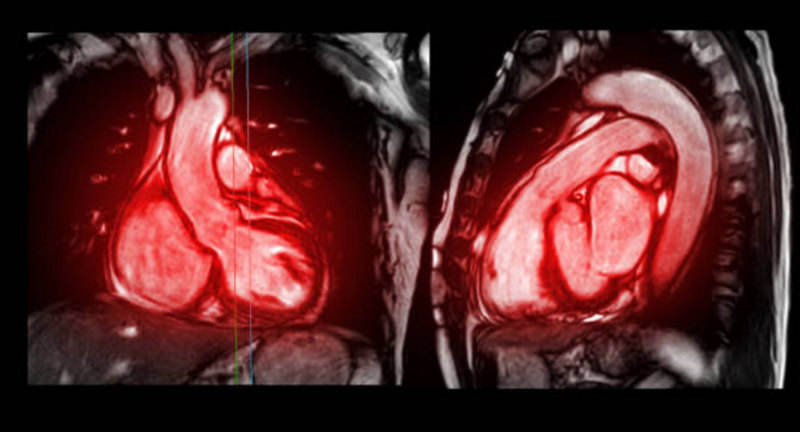

Cardiac MRI

A cardiac MRI (cardiovascular MRI or CMR) is a non-invasive imaging technique that uses magnetic fields and radio waves to create detailed images of the heart and blood vessels, aiding in the diagnosis and monitoring of various heart conditions.

What is Heart MRI?

How it works?

- A large magnet and radio waves are used to create images of the heart and blood vessels.

- The MRI machine creates a strong magnetic field around the body, and radio waves then disrupt the alignment of the hydrogen atoms in the body.

- As these atoms realign, they emit signals that are detected by the machine and used to create images.

- A computer processes these signals to create detailed images of the heart.

What it can show?

- Heart structure: Chambers, valves, and blood vessels.

- Heart function: How well the heart pumps blood.

- Heart muscle: Damage or disease in the heart muscle.

- Blood flow: Assessing blood flow to and from the heart.

- Other conditions: Tumors, inflammation, and other heart-related issues.